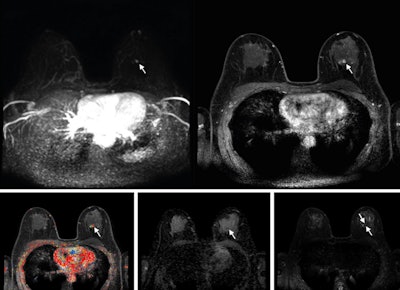

Abbreviated axial MRI images show a 7-mm irregular mass with irregular margin (arrows) in the right upper inner quadrant with early rapid enhancement (BIRADS 4). The participant was recalled and underwent an MRI-guided vacuum-assisted biopsy that showed sclerosing adenosis with microcalcifications and usual ductal hyperplasia and focal apocrine metaplasia. On the full-protocol images (not shown), the lesion was T2-weighted hypointense and showed diffusion restriction and washout kinetics in the delayed phase, characteristics that would not have reversed the decision to recall the participant.RSNA

Abbreviated axial MRI images show a 7-mm irregular mass with irregular margin (arrows) in the right upper inner quadrant with early rapid enhancement (BIRADS 4). The participant was recalled and underwent an MRI-guided vacuum-assisted biopsy that showed sclerosing adenosis with microcalcifications and usual ductal hyperplasia and focal apocrine metaplasia. On the full-protocol images (not shown), the lesion was T2-weighted hypointense and showed diffusion restriction and washout kinetics in the delayed phase, characteristics that would not have reversed the decision to recall the participant.RSNA